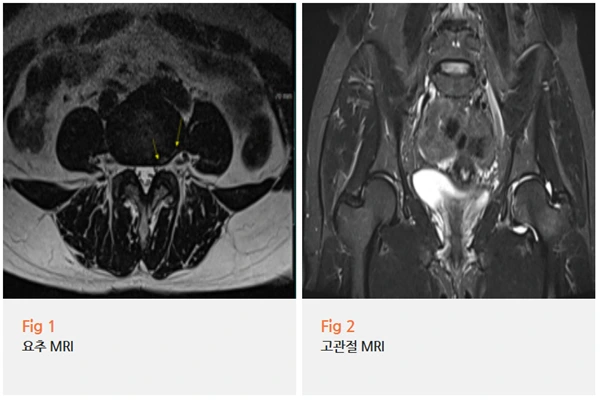

당일 요추 MRI와 고관절 MRI를 함께 촬영했는데요.

결과를 보는 순간 '역시나' 싶었어요.

✅ 요추 4-5번 추간판에 문제가 있었고

✅ 좌측 고관절 부위에 염증 소견이 명확하게 보였어요

✅ 게다가 고관절 충돌 증후군까지 확인됐죠